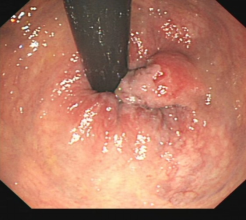

消化道早癌的病例展示(经内镜手术或活检证实):

胃角的腺癌